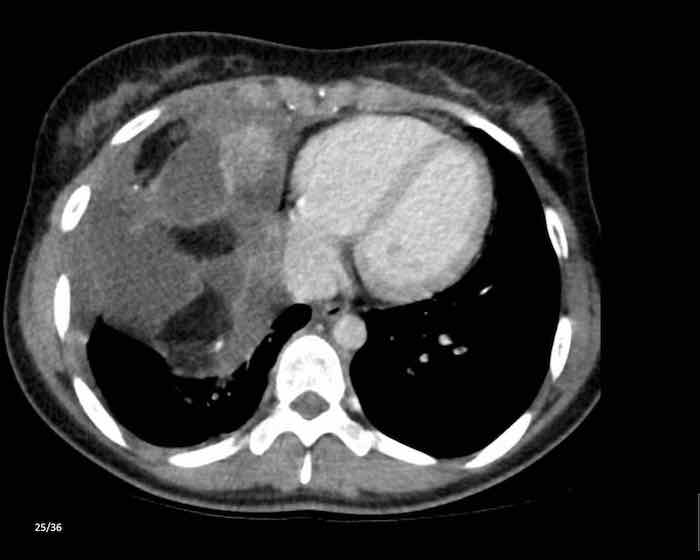

Các hình ảnh này của một phụ nữ 65 tuổi có tiền sử mắc bệnh Graves, một rối loạn tự miễn liên quan đến tình trạng cường chức năng tuyến giáp.

CT được thực hiện vì lý do ho ra máu.

Hình ảnh

Có một tuyến ức to lớn, cồng kềnh chứa mô mỡ đại thể.

Đây là hình ảnh điển hình của tăng sản tuyến ức.

Tăng sản tuyến ức trong bệnh Graves có liên quan đến tình trạng dư thừa hormone tuyến giáp và kháng thể kháng thụ thể thyrotropin.

Tình trạng này thường cải thiện sau khi điều trị thành công bệnh Graves.